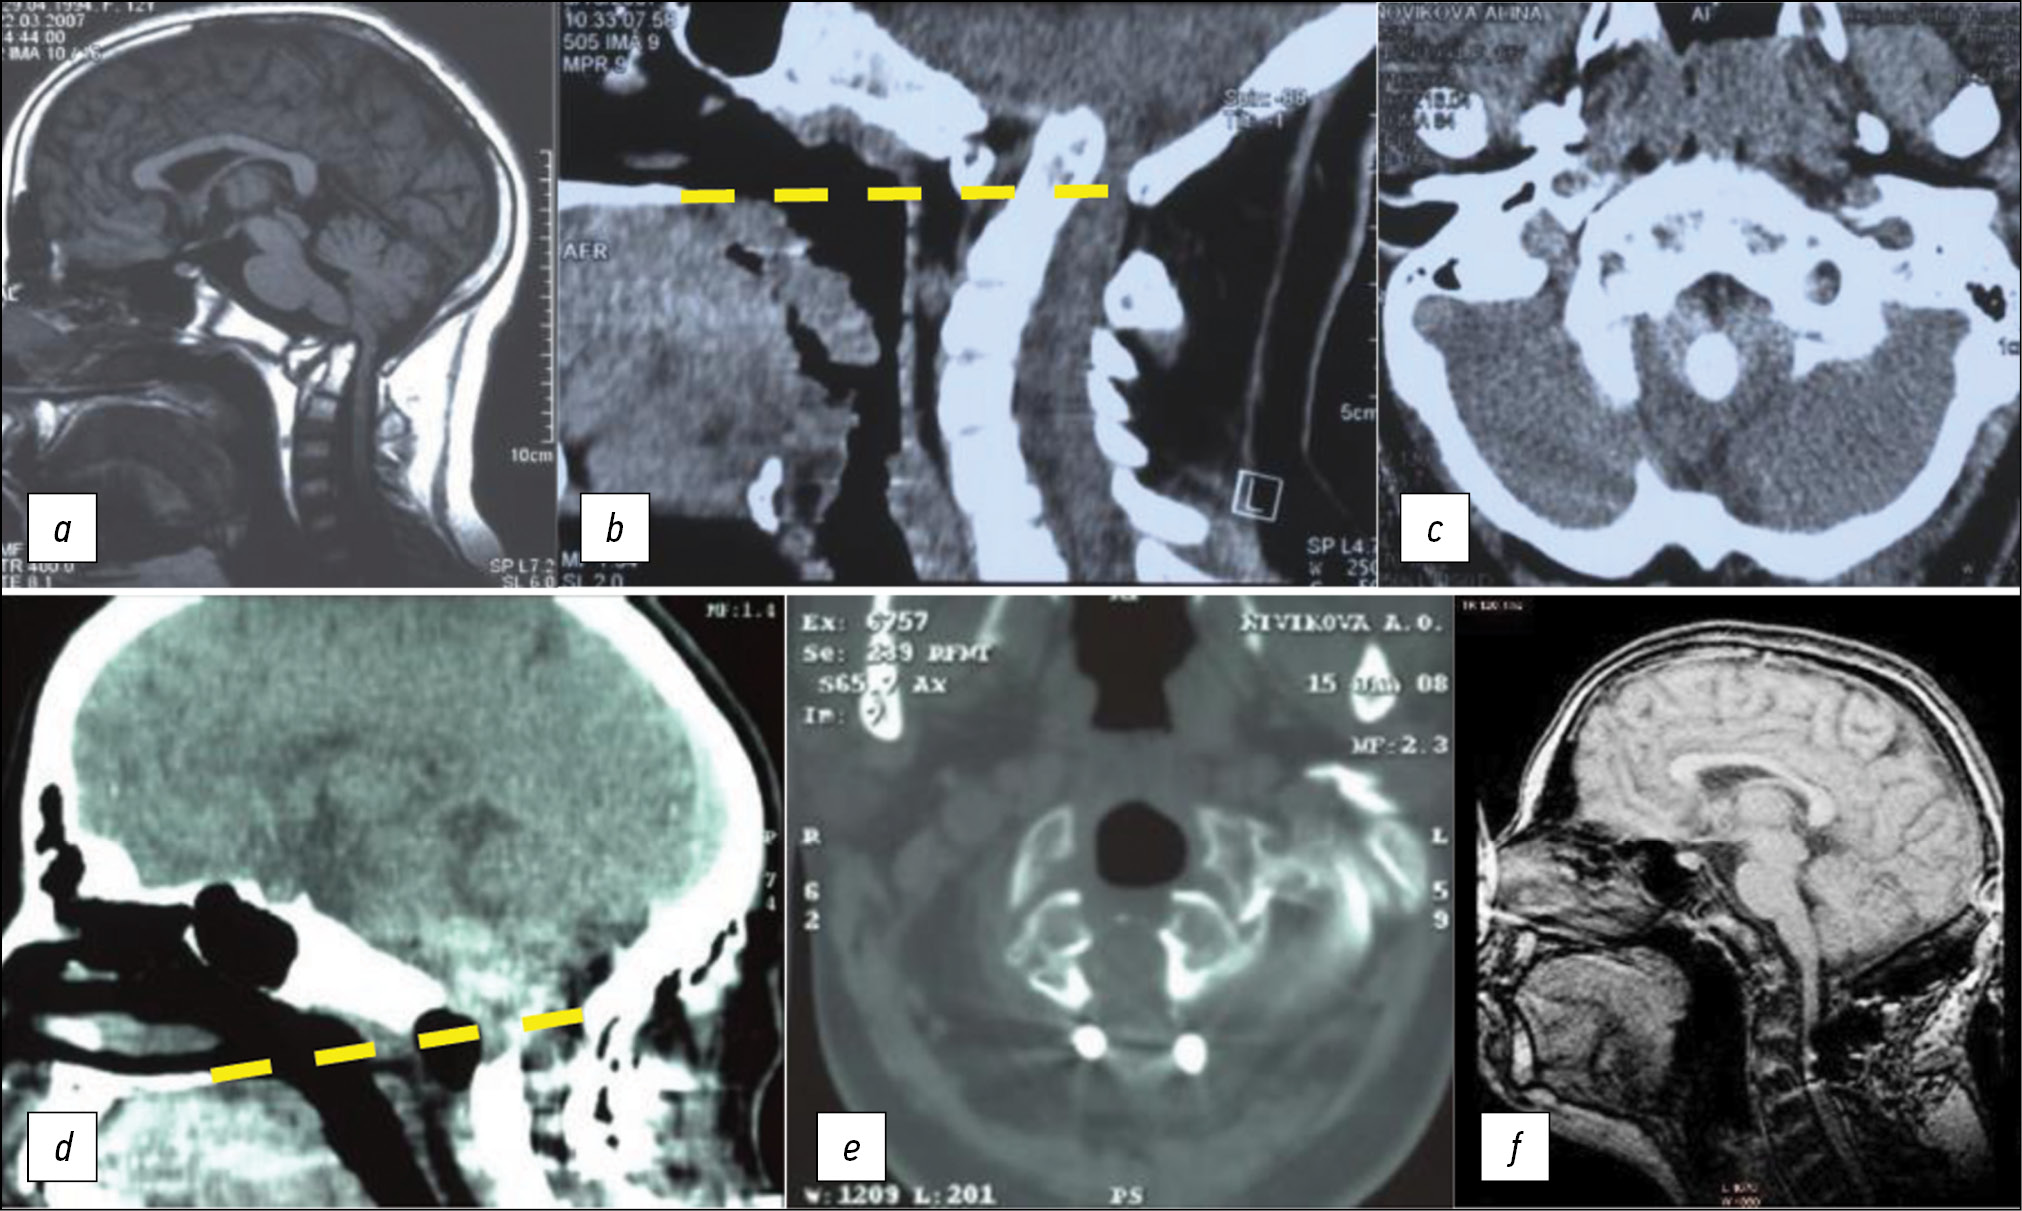

The results of surgical treatment were evaluated based on a retrospective analysis of the case histories of five patients whose odontoid process of the CII vertebra was removed endoscopically transnasally (clinical case in Fig. 2).

Fig. 2. Neuroimaging studies of patient K., 27 years old, before and after surgery.

Note. a — magnetic resonance imaging (MRI) before surgery. b — spiral computed tomography (SCT) before surgery. Invagination of the CII vertebra odontoid compression of the medulla oblongata is determined. The red dotted line is the line of the plane of McRae’s foramen magnum. The yellow dotted line indicates the Chamberlain line. The red arrow indicates the direction of access. The operating angle is 25 °. c — MRI before surgery, syringomyelitic cyst CIII–ThVII. In the clinical picture — headache, hemiparesis 4 points. d — SCT 7 days after the operation. e — SCT 3 months after surgery. f — MRI of the head and neck in the sagittal projection in T1 mode. Decompression of the medulla oblongata and spinal cord, almost complete regression of the giant syringomyelitic cyst.

Preoperative CVJ instability was not observed in any of the cases. Stabilization (OSD with the Vertex system) was performed in two patients, 1 and 3 months before the main stage of treatment. In two other patients, stabilization was performed simultaneously, as part of a two-stage surgical treatment. One of them (diagnosed with basilar impression, invagination of the odontoid process, syringomyelitic cyst at the level of CIII to ThIII vertebrae) underwent posterior decompression of the CVJ level during posterior stabilization. In one patient (diagnosed with intussusception of the odontoid process, Chiari anomaly type 1), CVJ was not stabilized. Despite the lack of assimilation of the CI vertebra with the skull, and after 3 months of wearing a Philadelphia collar, the CVJ stabilization was registered.

In the range of complications, the development of pneumonia was also registered in one case after surgery. Clinical symptom assessment was performed at the time of patient discharge. Positive changes were noted in two patients with initial tetraparesis, as they experienced a complete restoration of strength in the limbs. In one patient without initial motor impairment, deterioration was noted with the development of tetraparesis up to four points. In three out of four patients with cranialgia after surgery, regression of headache was recorded, while in one patient, no dynamics was registered. The only patient with ataxy showed regression of unsteady gait after surgery. All patients with sensory abnormalities had their regression in the early postoperative period (Fig. 3). A patient with Arnold–Chiari anomaly in the early postoperative period (day 7 after surgery) had a partial redislocation from the cerebellar tonsils of 19–15 mm and further redislocation up to 7 mm during 3 months of follow-up.